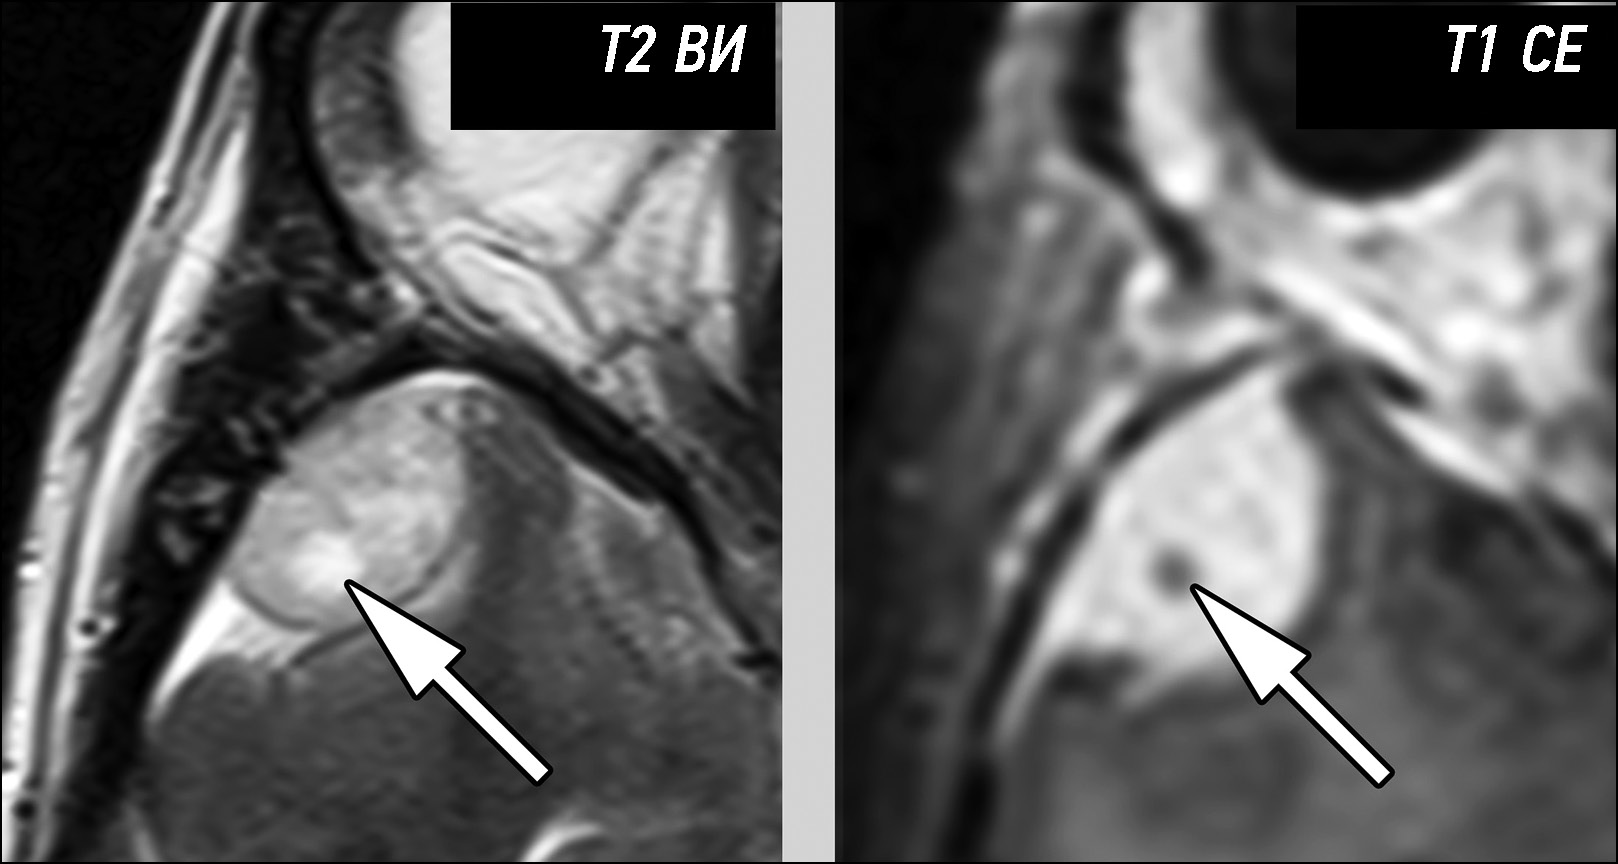

Primary extracerebral tumors are represented by benign and malignant neoplasms of the meninges and cranial nerves. Their presurgical differential diagnosis is based on the analysis of magnetic resonance imaging semiotics. The critically significant aspects for classifying tumors of this group include the following: neoplasm structure, contrast enhancement type, delimiting from the brain tissue, and relationship with the meninges or cranial nerves. Differential diagnosis of extracerebral tumors based on visual analysis of magnetic resonance imaging data is generally not challenging because most tumors have typical magnetic resonance imaging semiotics. However, in cases with atypical magnetic resonance imaging signs, reliable differentiation of tumors can be challenging. Moreover, the greatest complexity is the differentiation of meningioma grades, distinction between solitary fibrous tumors and meningiomas, and identification of the tumor type when localized in the cerebellopontine angles. The case series presented the most typical features leading to errors in the differential diagnosis of primary extracerebral tumors. All the presented tumors were verified with postsurgical histological examination. The analysis of the case reports demonstrates that a review of the combined semiotic signs can lower the number of diagnostic errors.